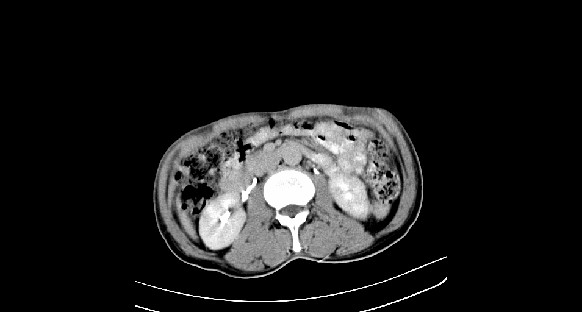

男性,70岁,体检b超发现左肾占位,请各位战友发表一下观点

左肾有两个病灶,且较大的病灶内可见点状钙化灶,增强扫描边缘也是呈渐进性强化,中央部分未见明显强化